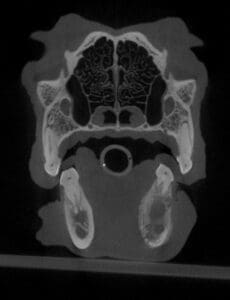

In the following case, the right lower first molar had chronic pulp exposure. This caused an infection in the bone (osteomyelitis) that spread beyond the tooth roots. Although this many changes in the bone can also be due to cancer, a biopsy confirmed that it was just infection. Again, extraction of the tooth fixed the problem, and the dog felt much better afterwards. Antibiotics were used because the infection in the bone was so extensive.